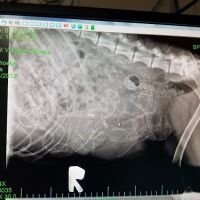

- Thorough and Detailed Explanations: Clients appreciate that the vets explain everything clearly, including X-rays and treatment options, without being pushy.

★ 5★ 4★ 3★ 2★ 1I hope I'm not speaking too soon, but Dr. Wendy recommended a shot called Solensia, and so far, it's doing the job! It does have potential side effects, so hopefully, this will help my kitty. She walked through the x-ray in great detail. She had thoroughly read all of the prior vets notes and was clear on the objectives. No pressure, lots of caring, and patience. I've already recommended Pet Stop Vet to others.